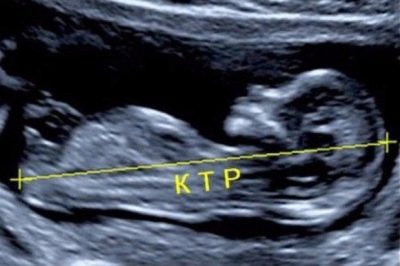

Ультразвуковое исследование во время беременности представляет собой ключевой диагностический метод. Оно помогает выявить различные патологии репродуктивной системы у беременной женщины и позволяет оценить параметры плода. Специалисты используют множество клинических критериев для анализа развития малыша.

Одним из таких критериев является копчико-теменной размер (КТР). На данном этапе беременности КТР составляет примерно 5 сантиметров и продолжает увеличиваться с каждым днем.

Норма КТР, сердцебиения плода и ХГЧ на этом сроке

КТР – это копчико-теменной размер плода, который измеряется специалистом во время проведения ультразвукового исследования. На одиннадцатой неделе этот размер должен составлять от 34 до 50 мм.